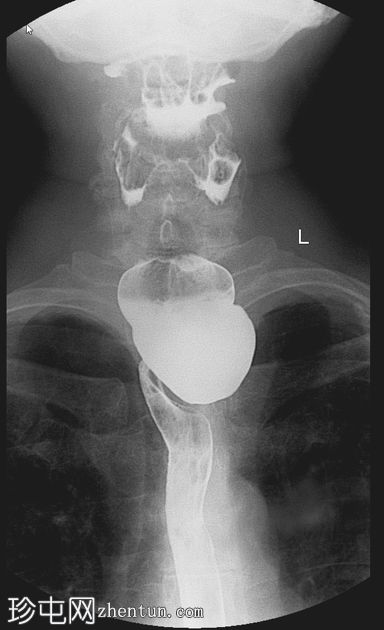

Zenker憩室

间歇性吞咽困难和未消化食物反流

年龄:65岁

性别:男

钡餐检查

可见一充满造影剂的、向后突出的憩室,位于咽食管交界处后壁,大致在T1椎体水平。憩室颈部狭窄,与颈段食管相通。吞咽时憩室充满造影剂,延迟显像显示造影剂滞留。食管其余部分管径和走行正常。未见远端梗阻。

Zenker 憩室是咽后壁的推进性(假性)憩室,起源于 Killian 裂隙。

表现为后正中线向外突出的囊状物,颈部狭窄,位于 T1(C5-C6)水平或略低于该水平。

钡餐侧位片显示最佳。